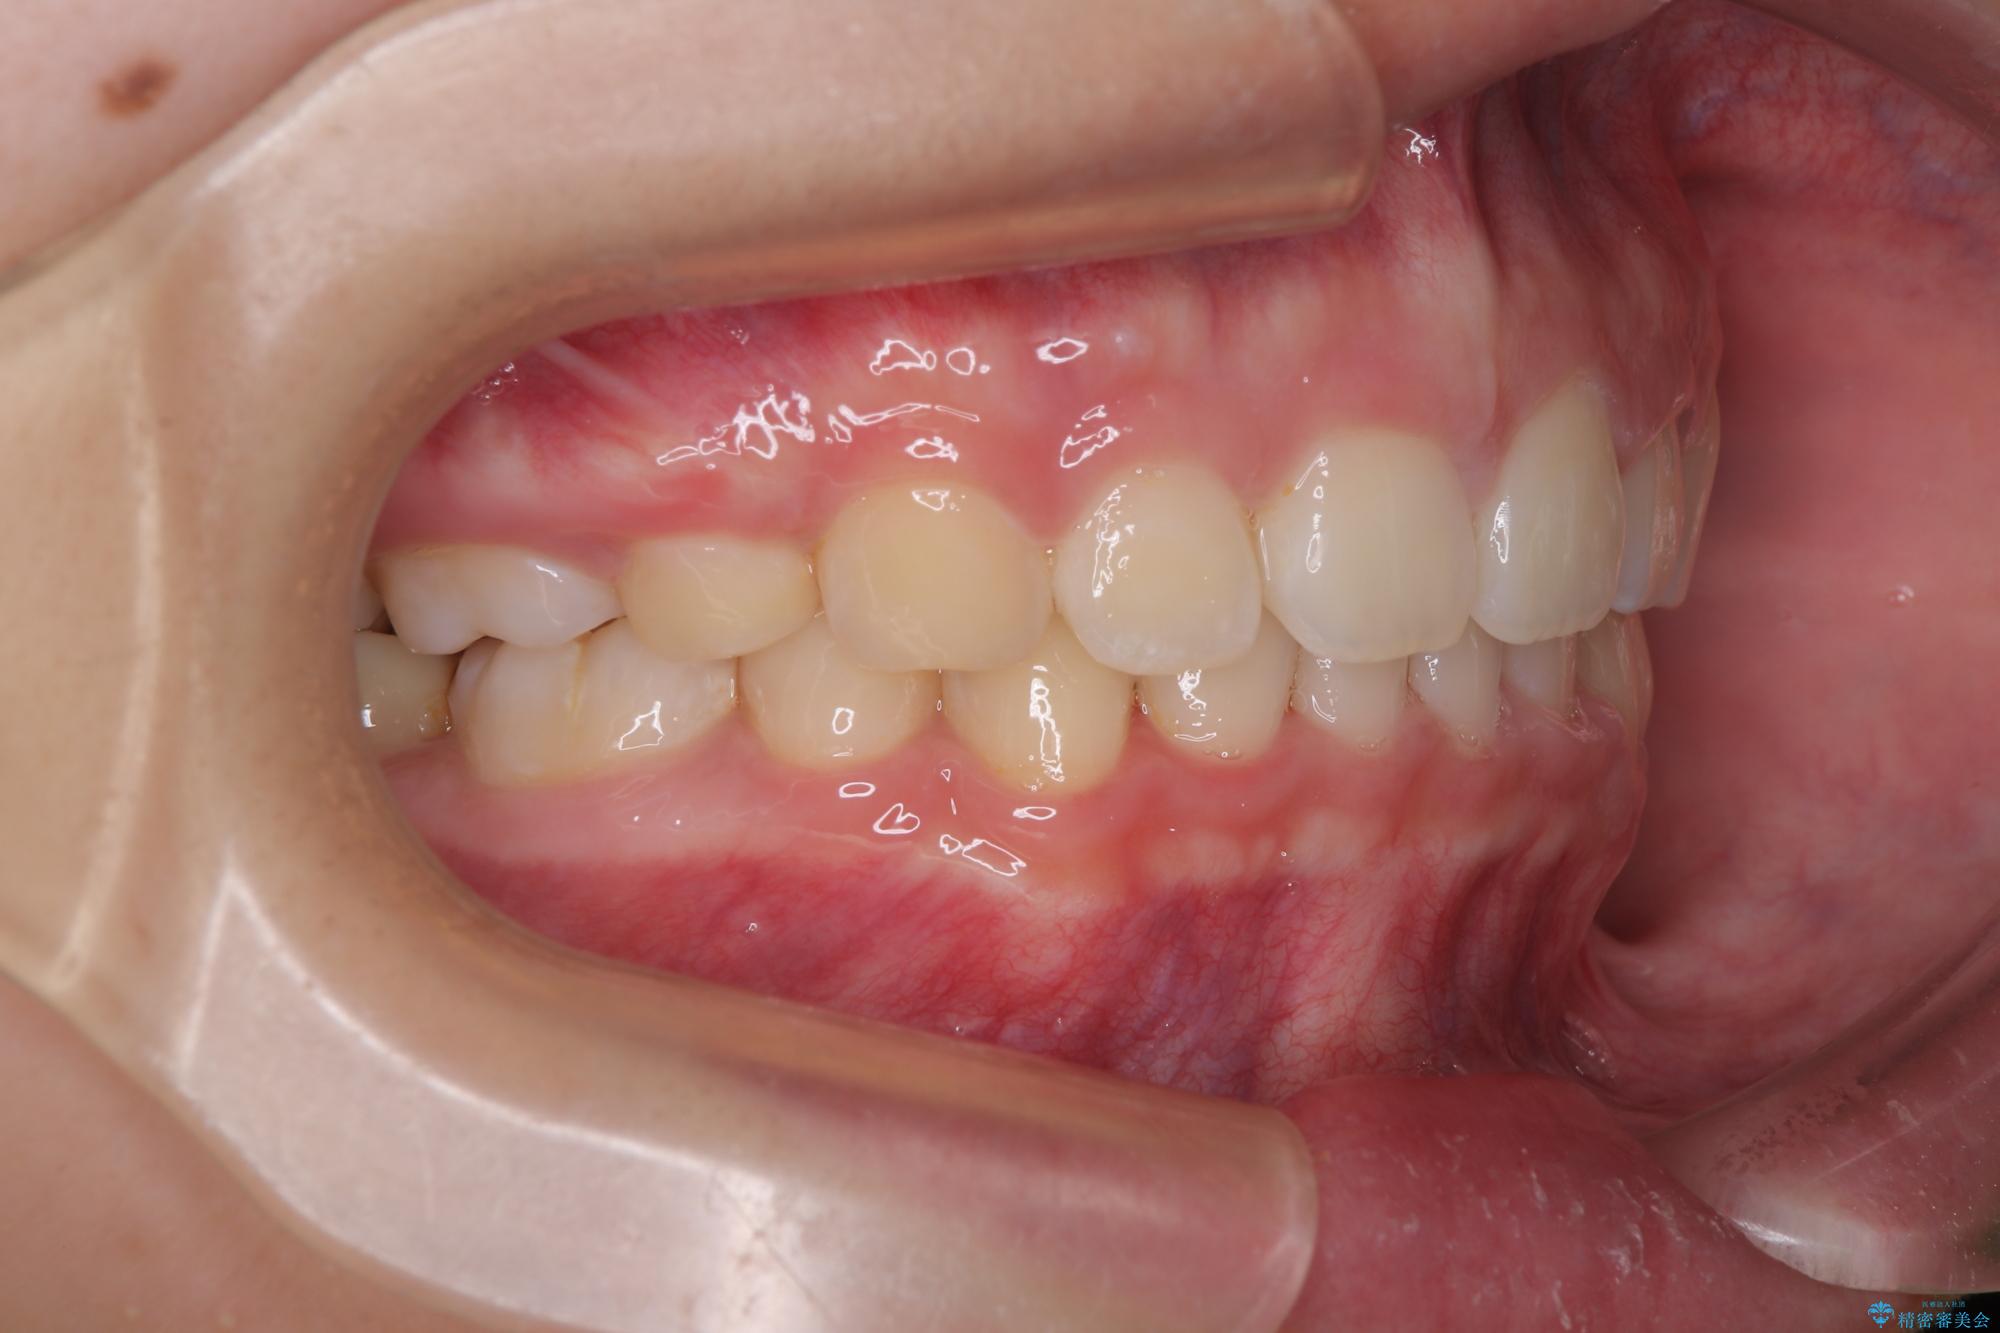

- 上顎前歯が飛び出していて唇がうまく閉じられないとのことで来院された患者様です。

くちばしのように前歯が突出していたため、口元を積極的に引っ込めるために、上下左右の小臼歯4本を抜歯することとしました。

また、上顎歯列が下顎に対して前方位に位置していたため、補助装置を用いて上顎歯列を後方に移動させ、より積極的に口元を下げるようにしました。

上下正中位置を改善するため、左下はイレギュラーに第二小臼歯を抜歯しました。そのため治療期間の長期化が予想されましたが、2年半ほどで期待通りの歯列に仕上げることができました。